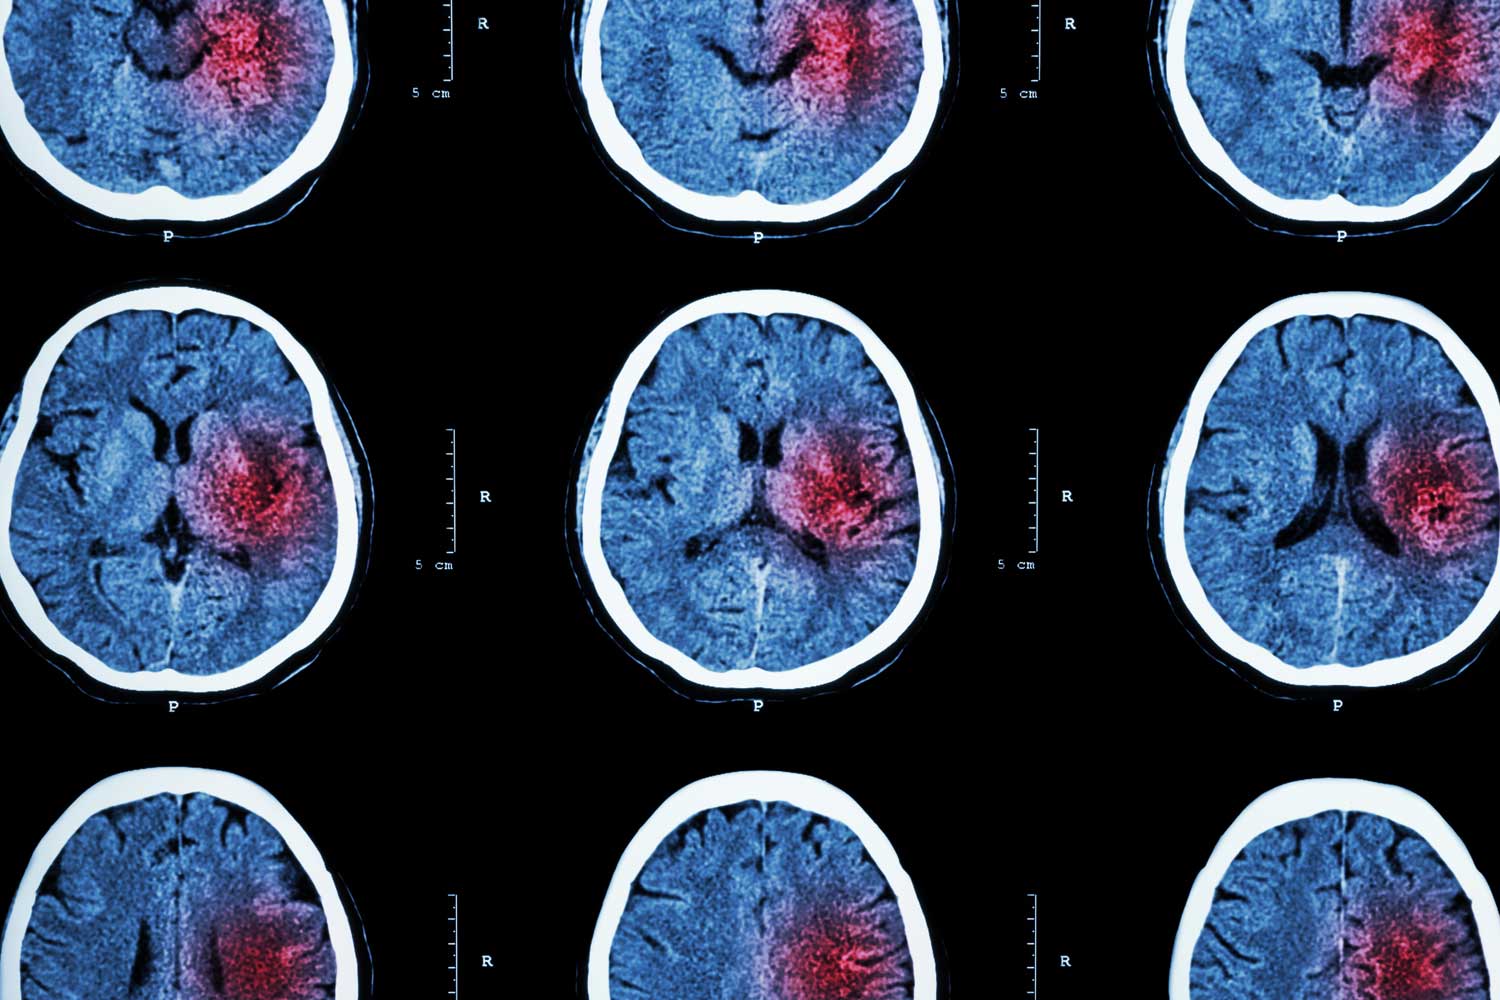

CT Scan (Computed Tomography)

A CT scan uses X-rays and computer technology to create detailed images of the brain. It’s often the first imaging test ordered because it can quickly show whether bleeding has occurred in the brain—a sign of a hemorrhagic stroke.

CT scans can also detect large areas of tissue damage from an ischemic stroke (caused by a blocked artery), though early ischemic changes may not be visible immediately. Doctors may also use specialized CT tests like CT angiography (CTA) to look closely at blood vessels in the head and neck.

An MRI scan uses magnetic fields and radio waves to produce highly detailed images of the brain. It’s often more sensitive than CT for detecting small or early ischemic strokes, especially when using advanced techniques like diffusion-weighted imaging.

MRI can show changes in brain tissue that might not be visible on a CT scan, making it especially useful for evaluating subtle strokes or assessing damage after symptoms have started.